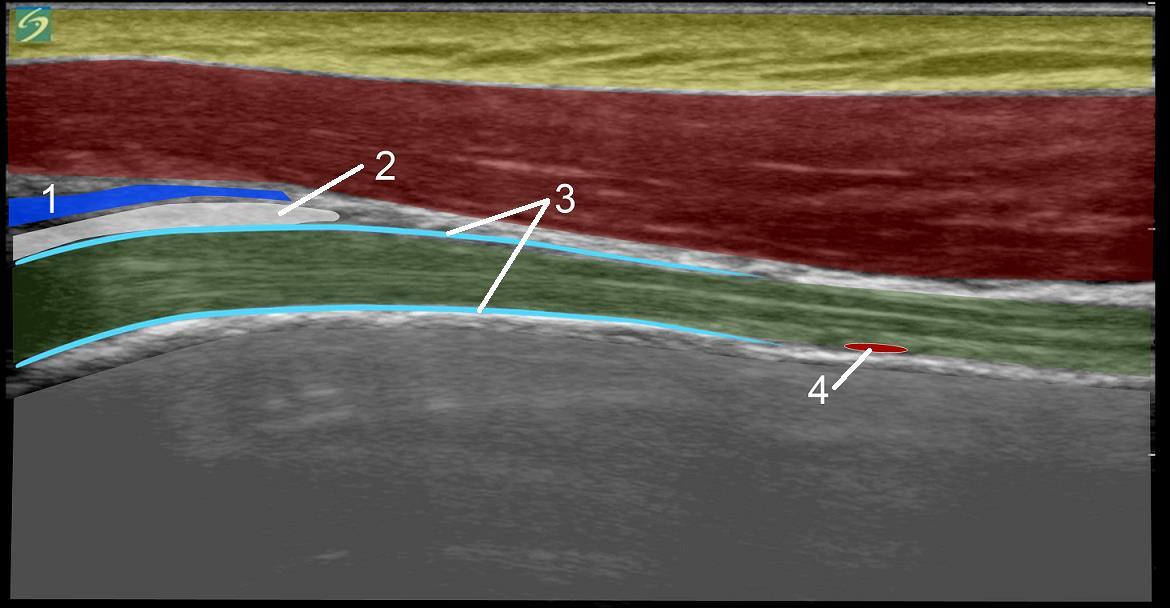

1. Bourse sous-acromiale

2. Ligament de l'humérus, Coupe transverse (section transverse)

3. Gaine du tendon du biceps

4. Artère humérale circonflexe antérieure